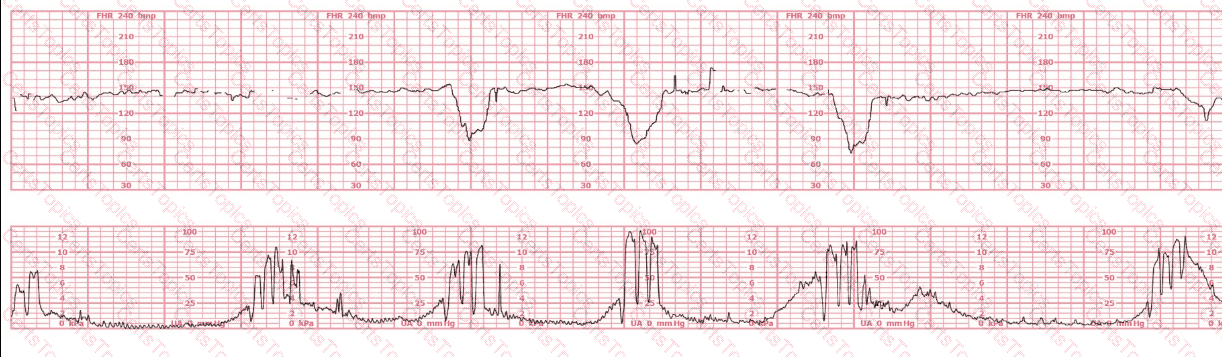

A woman at 38-weeks gestation is admitted to labor and delivery following a fall down the stairs three hours ago. She started feeling contractions in the ambulance. The fetal heart rate tracing shown is on initial evaluation and represents 25 minutes. This tracing is most consistent with a

A woman is admitted at 41-weeks gestation for fetal evaluation following a motor vehicle accident. She reports that she hit her abdomen on the steering wheel. The underlying physiology of the tracing is most likely:

A 30-year-old woman (G2P0) is experiencing preterm labor at 26-weeks gestation. She is receiving magnesium sulfate for neuroprotection. Her external fetal monitoring tracing over the past 30 minutes is shown. The next step would be to:

This tracing reflects: